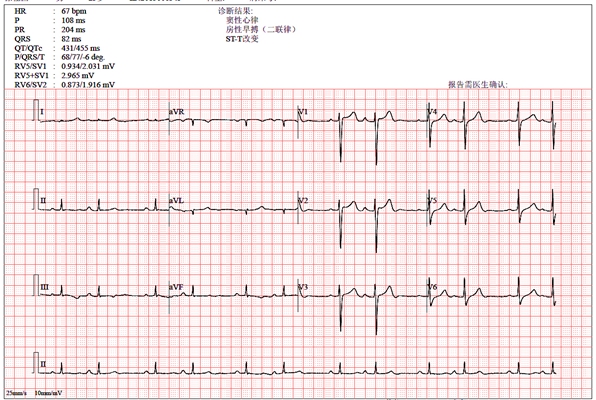

預激綜合徵心電圖 (9)

預激綜合徵心電圖 (90)

預激綜合徵心電圖 (91)

預激綜合徵心電圖 (92)

預激綜合徵心電圖 (93)

預激綜合徵心電圖 (94)

預激綜合徵心電圖 (95)

預激綜合徵心電圖 (96)

A:預激綜合徵典型的心電圖表現是竇性心搏的PR間期縮短,短於0.12s,而且導聯的QRS波群時間超過0.12s。QRS波群起始部分會有粗鈍,終末部分正常,甚至會導致ST-T波型呈現繼發性的改變,甚至於QRS波群主波方向相反。預激綜合徵是指心房……

A:預激綜合徵是很少見的心律失常,是房室傳導異常的一種類型,提早興奮心室的一部分或全部,引起心室肌提前激動,常合併室上性心動過速。心電圖可見PR間期縮短小於0.12秒;QRS時限延長0.11秒以上;QRS波群起始部粗鈍,繼發性ST-T改變。沒有……

A:預激綜合徵合併房速的時候,心電圖可以出現快速而且寬大畸形的QRS波群,有點類似於室性心動過速,典型的預激波有可能會被覆蓋。合併房速的時候會有極快速的心室率、QRS波群會寬大畸形,也有可能比較易變和複雜。患有預激綜合症合併房速,如果有明顯的心……